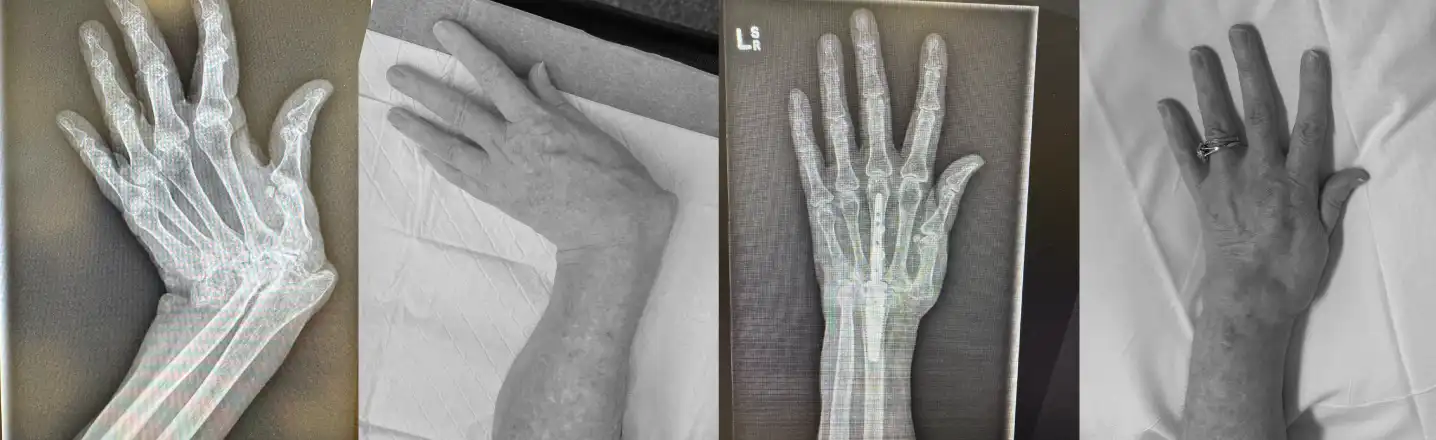

This challenging wrist reconstruction required a combination of advanced surgical techniques and careful multidisciplinary thinking:

• Deformity correction, drawing on Dr Sarah’s paediatric upper limb experience

• Use of the MotecWrist internal fusion system, keeping hardware within the wrist to minimise skin and tendon irritation

The outcome was a functional, sensate, and cosmetically acceptable hand—and, most importantly, a very happy patient.